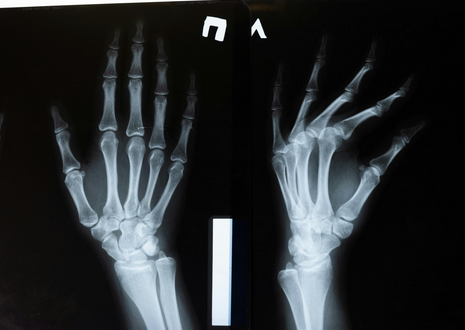

சென்னை: சீனாவைச் சேர்ந்த விஞ்ஞானிகள் உடைந்த எலும்புகளை மூன்றே நிமிடங்களில் சரிசெய்யக்கூடிய பசையை உருவாக்கியுள்ளதாகக் கூறியுள்ளனர். இன்றைய நவீன மருத்துவத் துறையில், ஒருவருக்கு எலும்பு முறிவு ஏற்பட்டால், எலும்பு முறிவின் தன்மையைப் பொறுத்து மருத்துவர்கள் சிகிச்சை அளிக்கின்றனர். சில நேரங்களில், அறுவை சிகிச்சை மூலம் உடைந்த எலும்புகளை சேர்க்க/இணைக்க உலோகம் பயன்படுத்தப்படுகிறது.

எலும்பு இணைக்கப்பட்ட பிறகு, பொருத்தப்பட்ட உலோகம் மீண்டும் அறுவை சிகிச்சை மூலம் அகற்றப்படுகிறது. சில சந்தர்ப்பங்களில், உடலில் உள்ள எலும்புடன் உலோகம் அப்படியே இருக்கும். இந்த சூழலில், சீனாவைச் சேர்ந்த விஞ்ஞானிகள் எலும்புகளை சரிசெய்யக்கூடிய மாற்று பசையை உருவாக்கியுள்ளதாக தெரிவிக்கப்பட்டுள்ளது. கிழக்கு சீனாவின் ஜெஜியாங் மாகாணத்தைச் சேர்ந்த மருத்துவர்கள் இதை உருவாக்கியுள்ளனர். சிப்பிகள் நீருக்கடியில் சில இடங்களில் உறுதியாக ஒட்டிக்கொள்வதைக் கவனித்த பிறகு, இந்த எலும்பு பசையை உருவாக்கும் யோசனை தனக்கு வந்ததாக எலும்பியல் அறுவை சிகிச்சை நிபுணர் லின் சியான்ஃபெங் கூறினார்.

உடைந்த எலும்புகளை மூன்றே நிமிடங்களில் இந்த பசை மூலம் சரிசெய்ய முடியும் என்று லின் கூறினார். எலும்புகள் குணமடையும் போது இந்த பசை தானாகவே கரைந்துவிடும் என்று அவர் கூறினார். ‘எலும்பு-02’ என்று அழைக்கப்படும் இந்த பசையின் செயல்திறன் மற்றும் பாதுகாப்பு, ஆய்வக சோதனைகள் மூலம் உறுதிப்படுத்தப்பட்டுள்ளது. மருத்துவர்கள் இதை சுமார் 150 பேரிடம் பரிசோதித்துள்ளனர்.

தற்போது, ​​எலும்பு சிமென்ட்கள் மற்றும் வெற்றிட நிரப்பிகள் சந்தையில் கிடைக்கின்றன. இருப்பினும், ‘எலும்பு-02’ எலும்புகளை பிணைக்கக்கூடிய பசையாக அறிவிக்கப்பட்டுள்ளது. இது உலகளவில் அறிமுகப்படுத்தப்படும்போது, ​​எலும்பு முறிவு சிகிச்சையில் பெரிய மாற்றத்தை ஏற்படுத்தும் என்று எதிர்பார்க்கப்படுகிறது. இது உலோக உள்வைப்புகளின் தேவையை நீக்கும்.